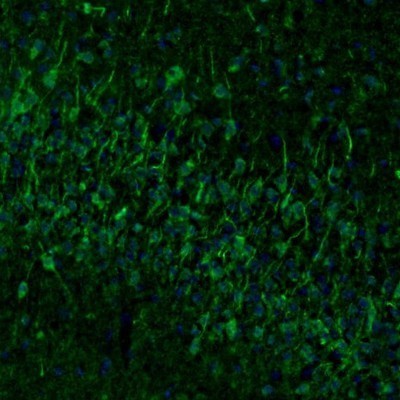

Supportive validation

- Submitted by

- Novus Biologicals (provider)

- Main image

- Experimental details

- Immunohistochemistry-Paraffin: Njmu-R1 Antibody [NBP1-82563] - Staining of mouse somatosensory cortex shows immunoreactivity in cell bodies and dendrites of pyramidal neurons.